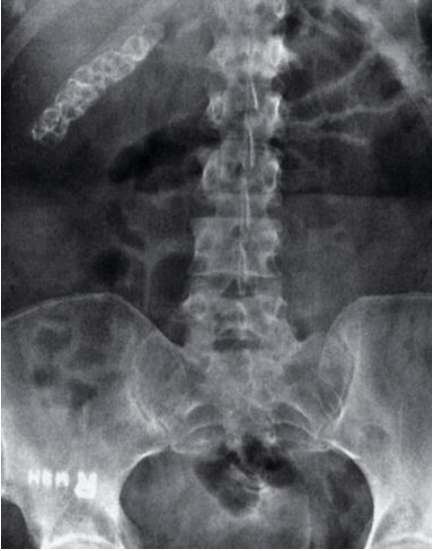

Observe a imagem abaixo. Mulher de 44 anos de idade se apresenta com dor.

A respeito do diagnótico mais provável, assinale a alternativa correta.